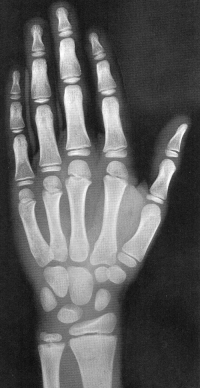

Sexo Masculino

17 anos

Fonte: GREULICH, W.W. & PYLE, S.I.: Radiografic Atlas of Development of the Hand and Wrist. Stanford University Press, 2° edition, 1959.